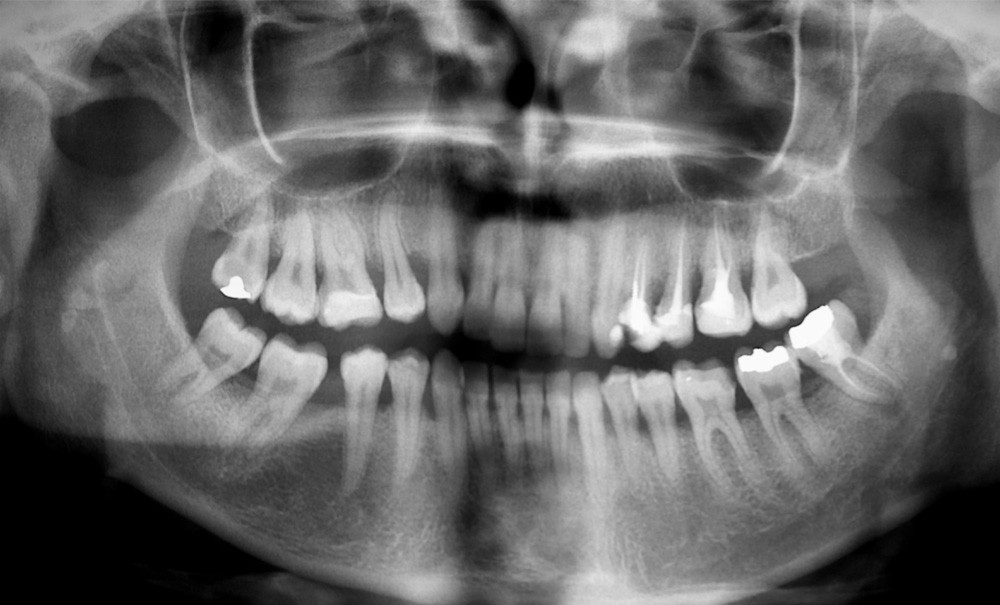

L’obésité, définie par un indice de masse corporelle (IMC) ≥ 30 kg/m2, est une maladie inflammatoire chronique complexe et multifactorielle caractérisée par un dépôt excessif de graisse dans le tissu adipeux. Selon l’OMS, depuis 1975, le nombre de cas d’obésité a presque triplé à l’échelle planétaire [1]. En 2020, près d’un Français sur deux était en surpoids, tandis que 17 % étaient obèses [2]. Or l’obésité est responsable d’une haute mortalité à l’échelle mondiale et est un facteur de risque majeur pour de nombreuses maladies, dont les maladies cardiovasculaires, le diabète de type 2 et certains cancers [1]. Son impact sur la santé des populations et son coût économique et social sont donc considérables. Ces deux dernières décennies, de nombreuses études ont montré que l’obésité pouvait aussi être incriminée dans la détérioration de la santé bucco-dentaire [3] (fig. 1 à 7).